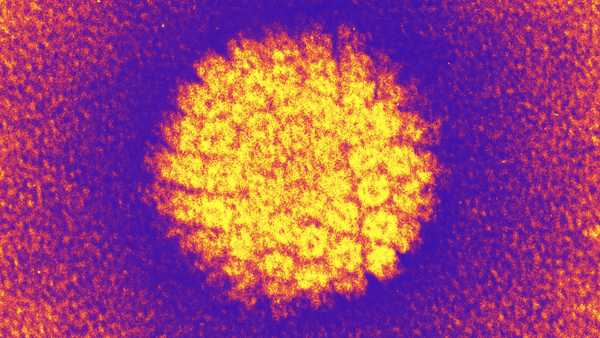

Вакцини проти ВПЛ довели свою високу ефективність. (Зображення: MicroStockHub via Getty Images)

Віруси ВПЛ можуть спричиняти рак шийки матки та інші види раку.